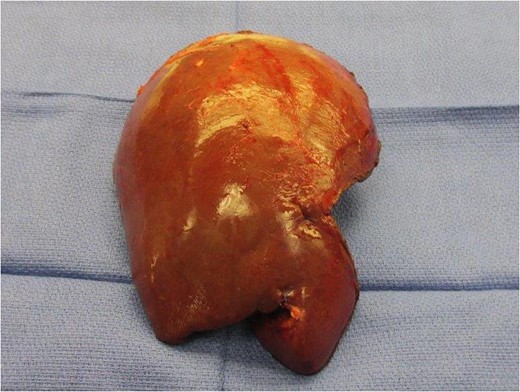

Liver pathologic evaluation revealed microscopic foci of metastatic adenocarcinoma in a background of necrosis in segment VIII without any additional lesions. Colon pathologic analysis showed a 5-cm tubulovillous adenoma with moderately differentiated adenocarcinoma. It also found high-grade SCC that infiltrated into pericolonic fat with lymphovascular and perineural invasion. A 4-cm tubulovillous adenoma with moderately differentiated adenocarcinoma was entering the muscularis propria. All margins were negative. Five of 20 lymph nodes were positive for SCC and adenocarcinoma (pT3pN2apM1a).